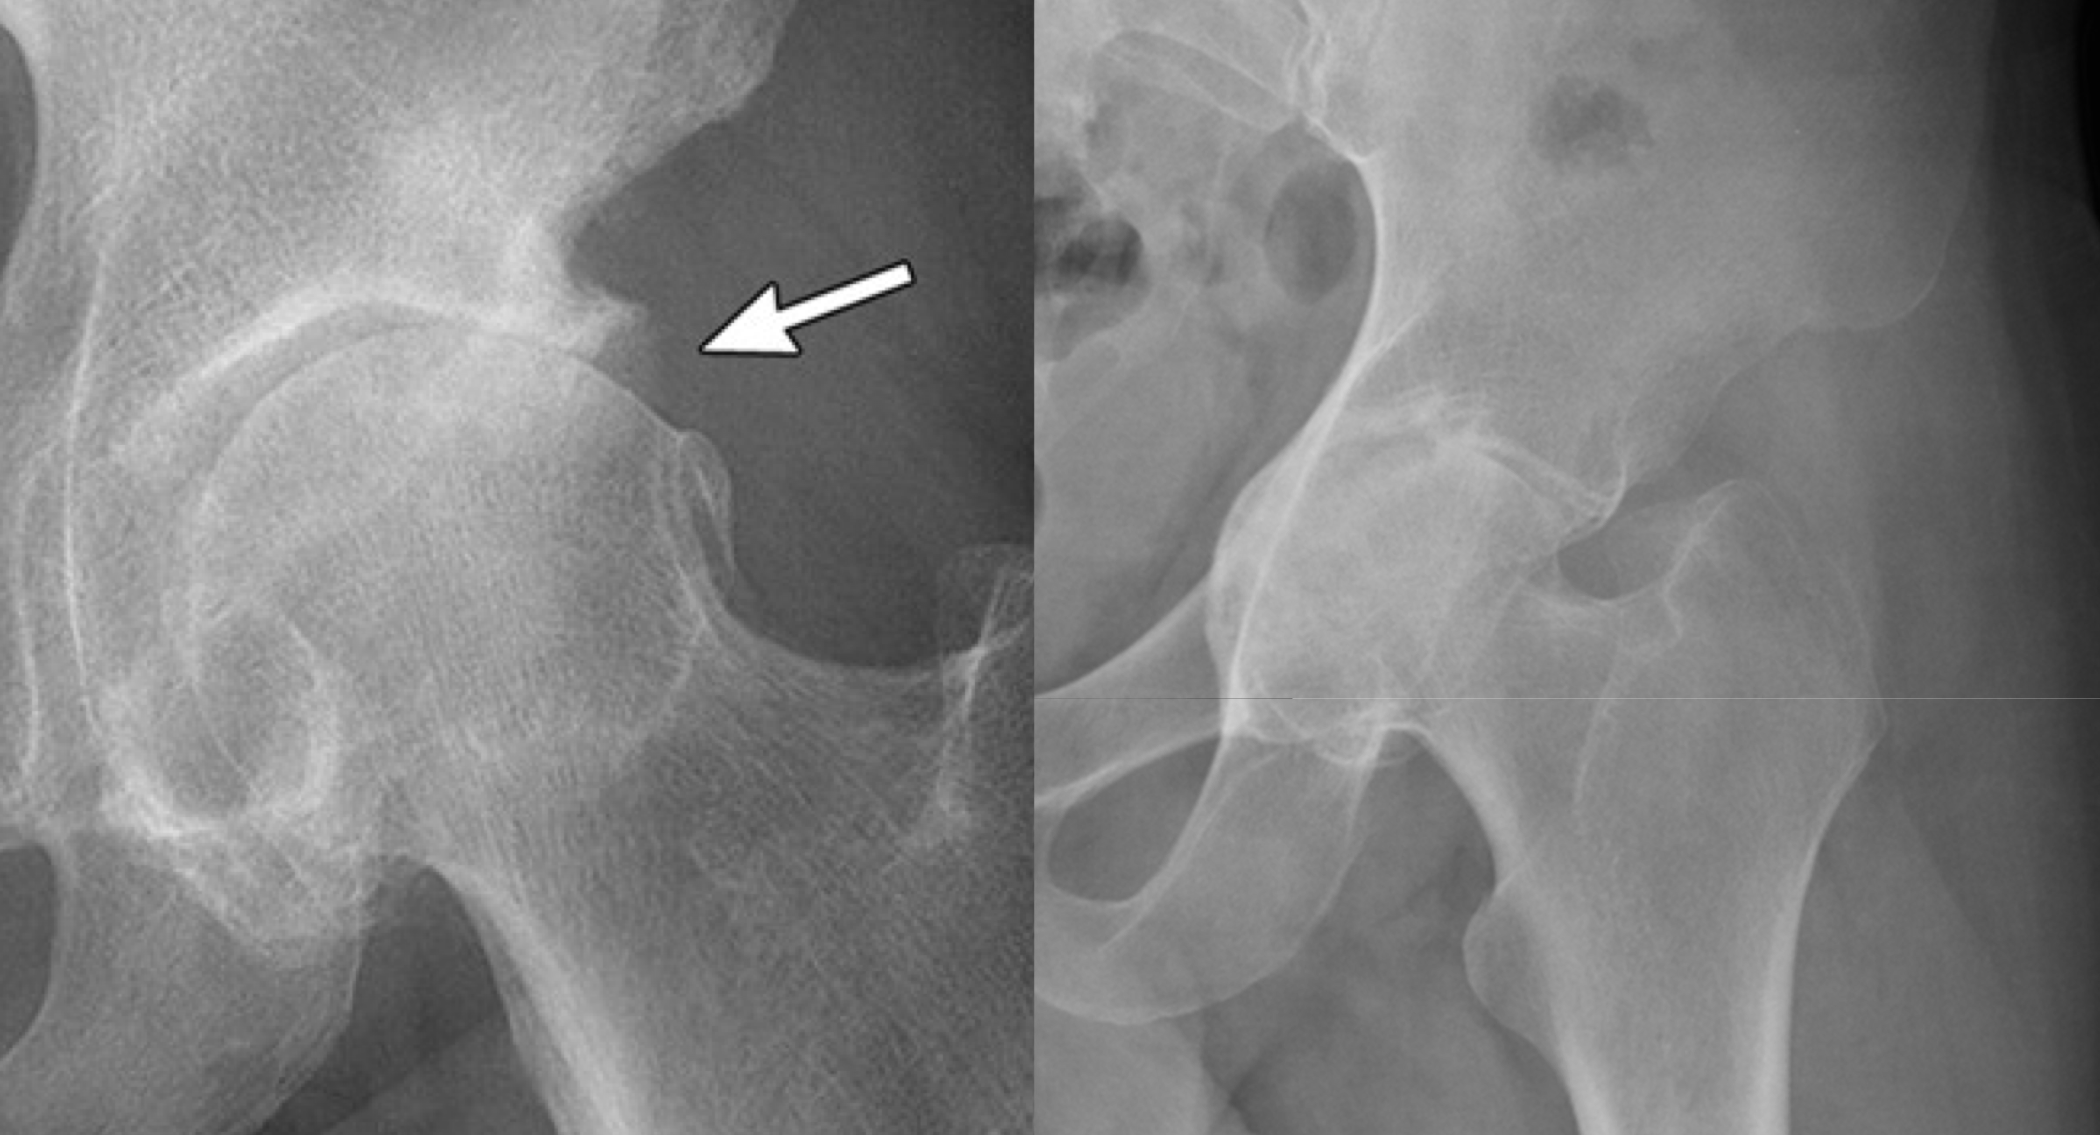

Why is this image’s dx NOT Osteitis Condensans Ilii (OCI)

b/c erosions

What are the two dx of these images (left vs right)

Left = PsA

Right = AS